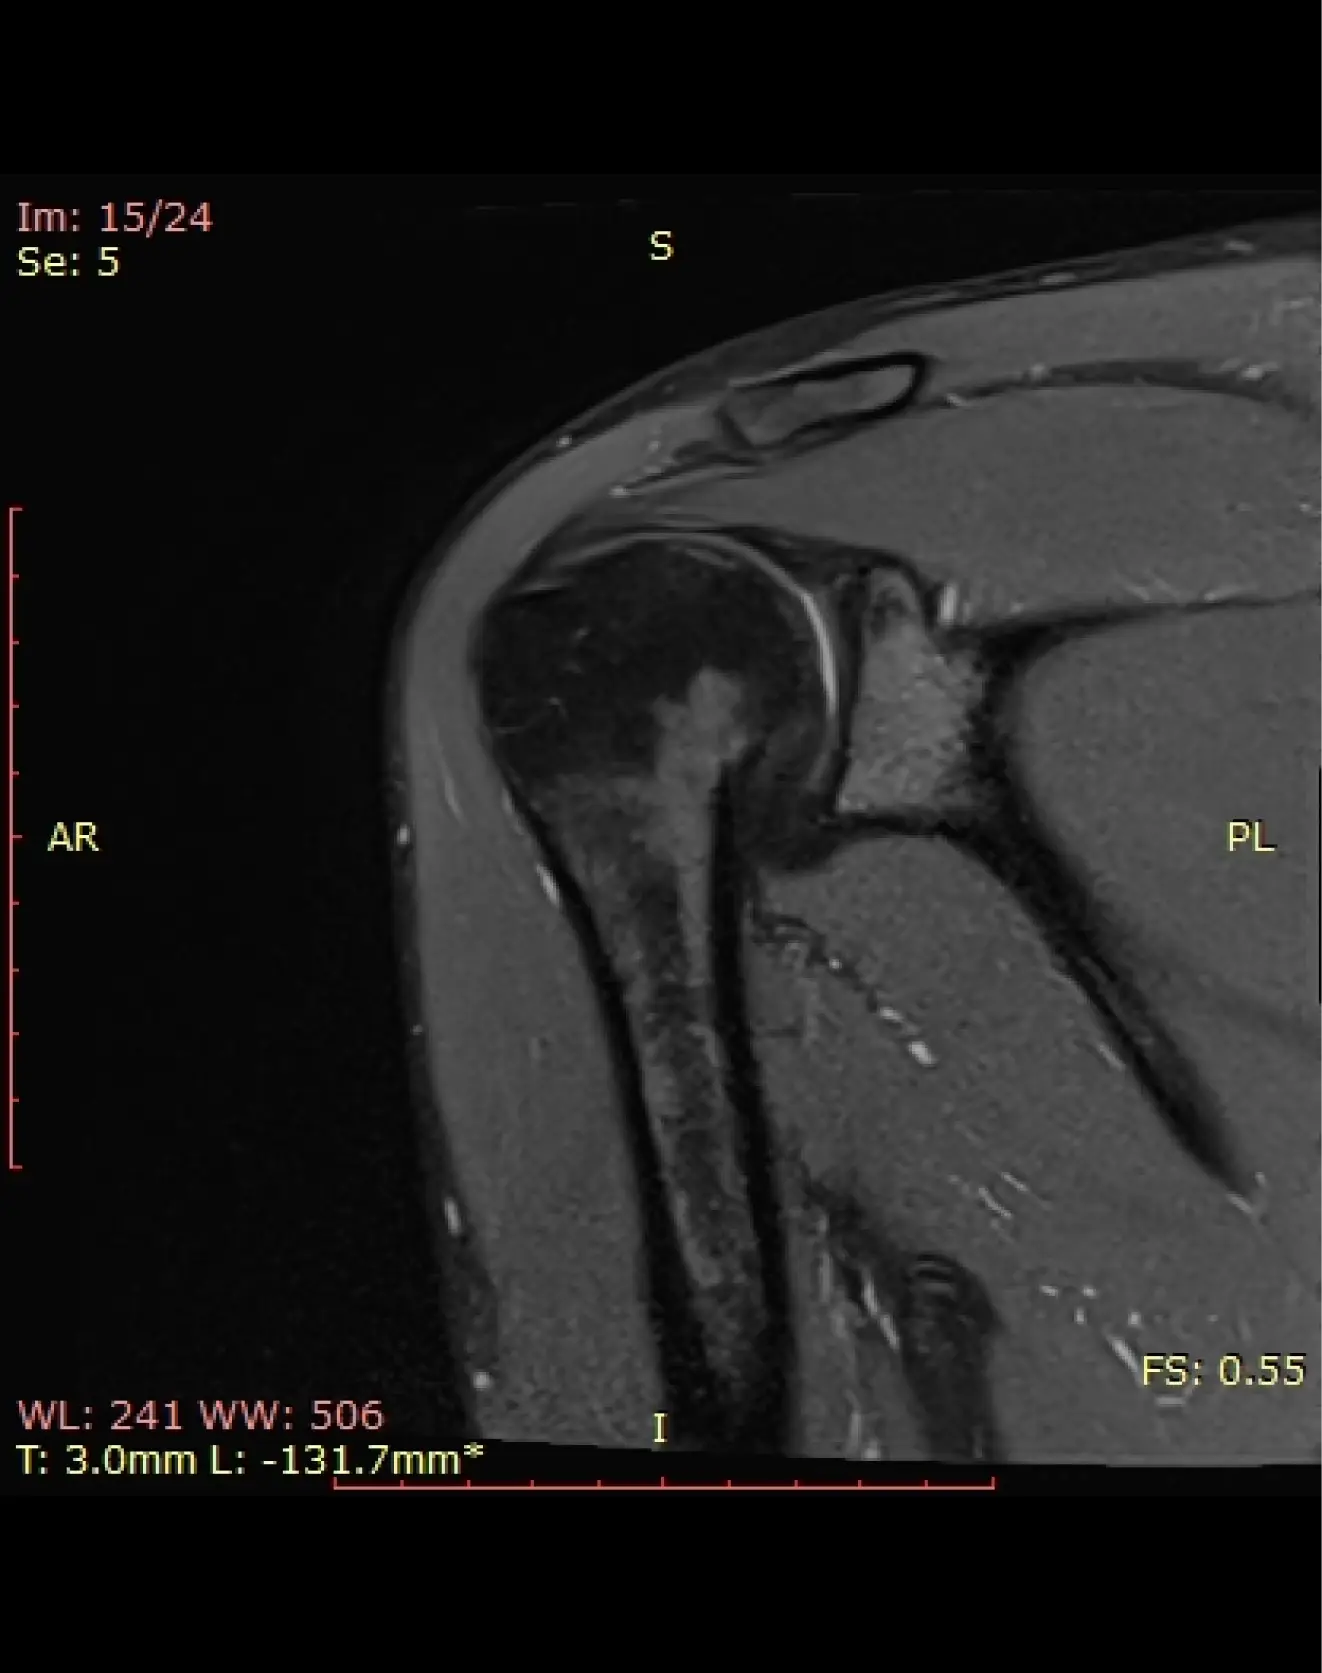

МРТ плечевого сустава

Визуализация костей плечевого сустава, суставной губы, удерживающих сухожилий и связок, регионарных мышц, околосуставных сумок, ключично-акромиального сочленения.